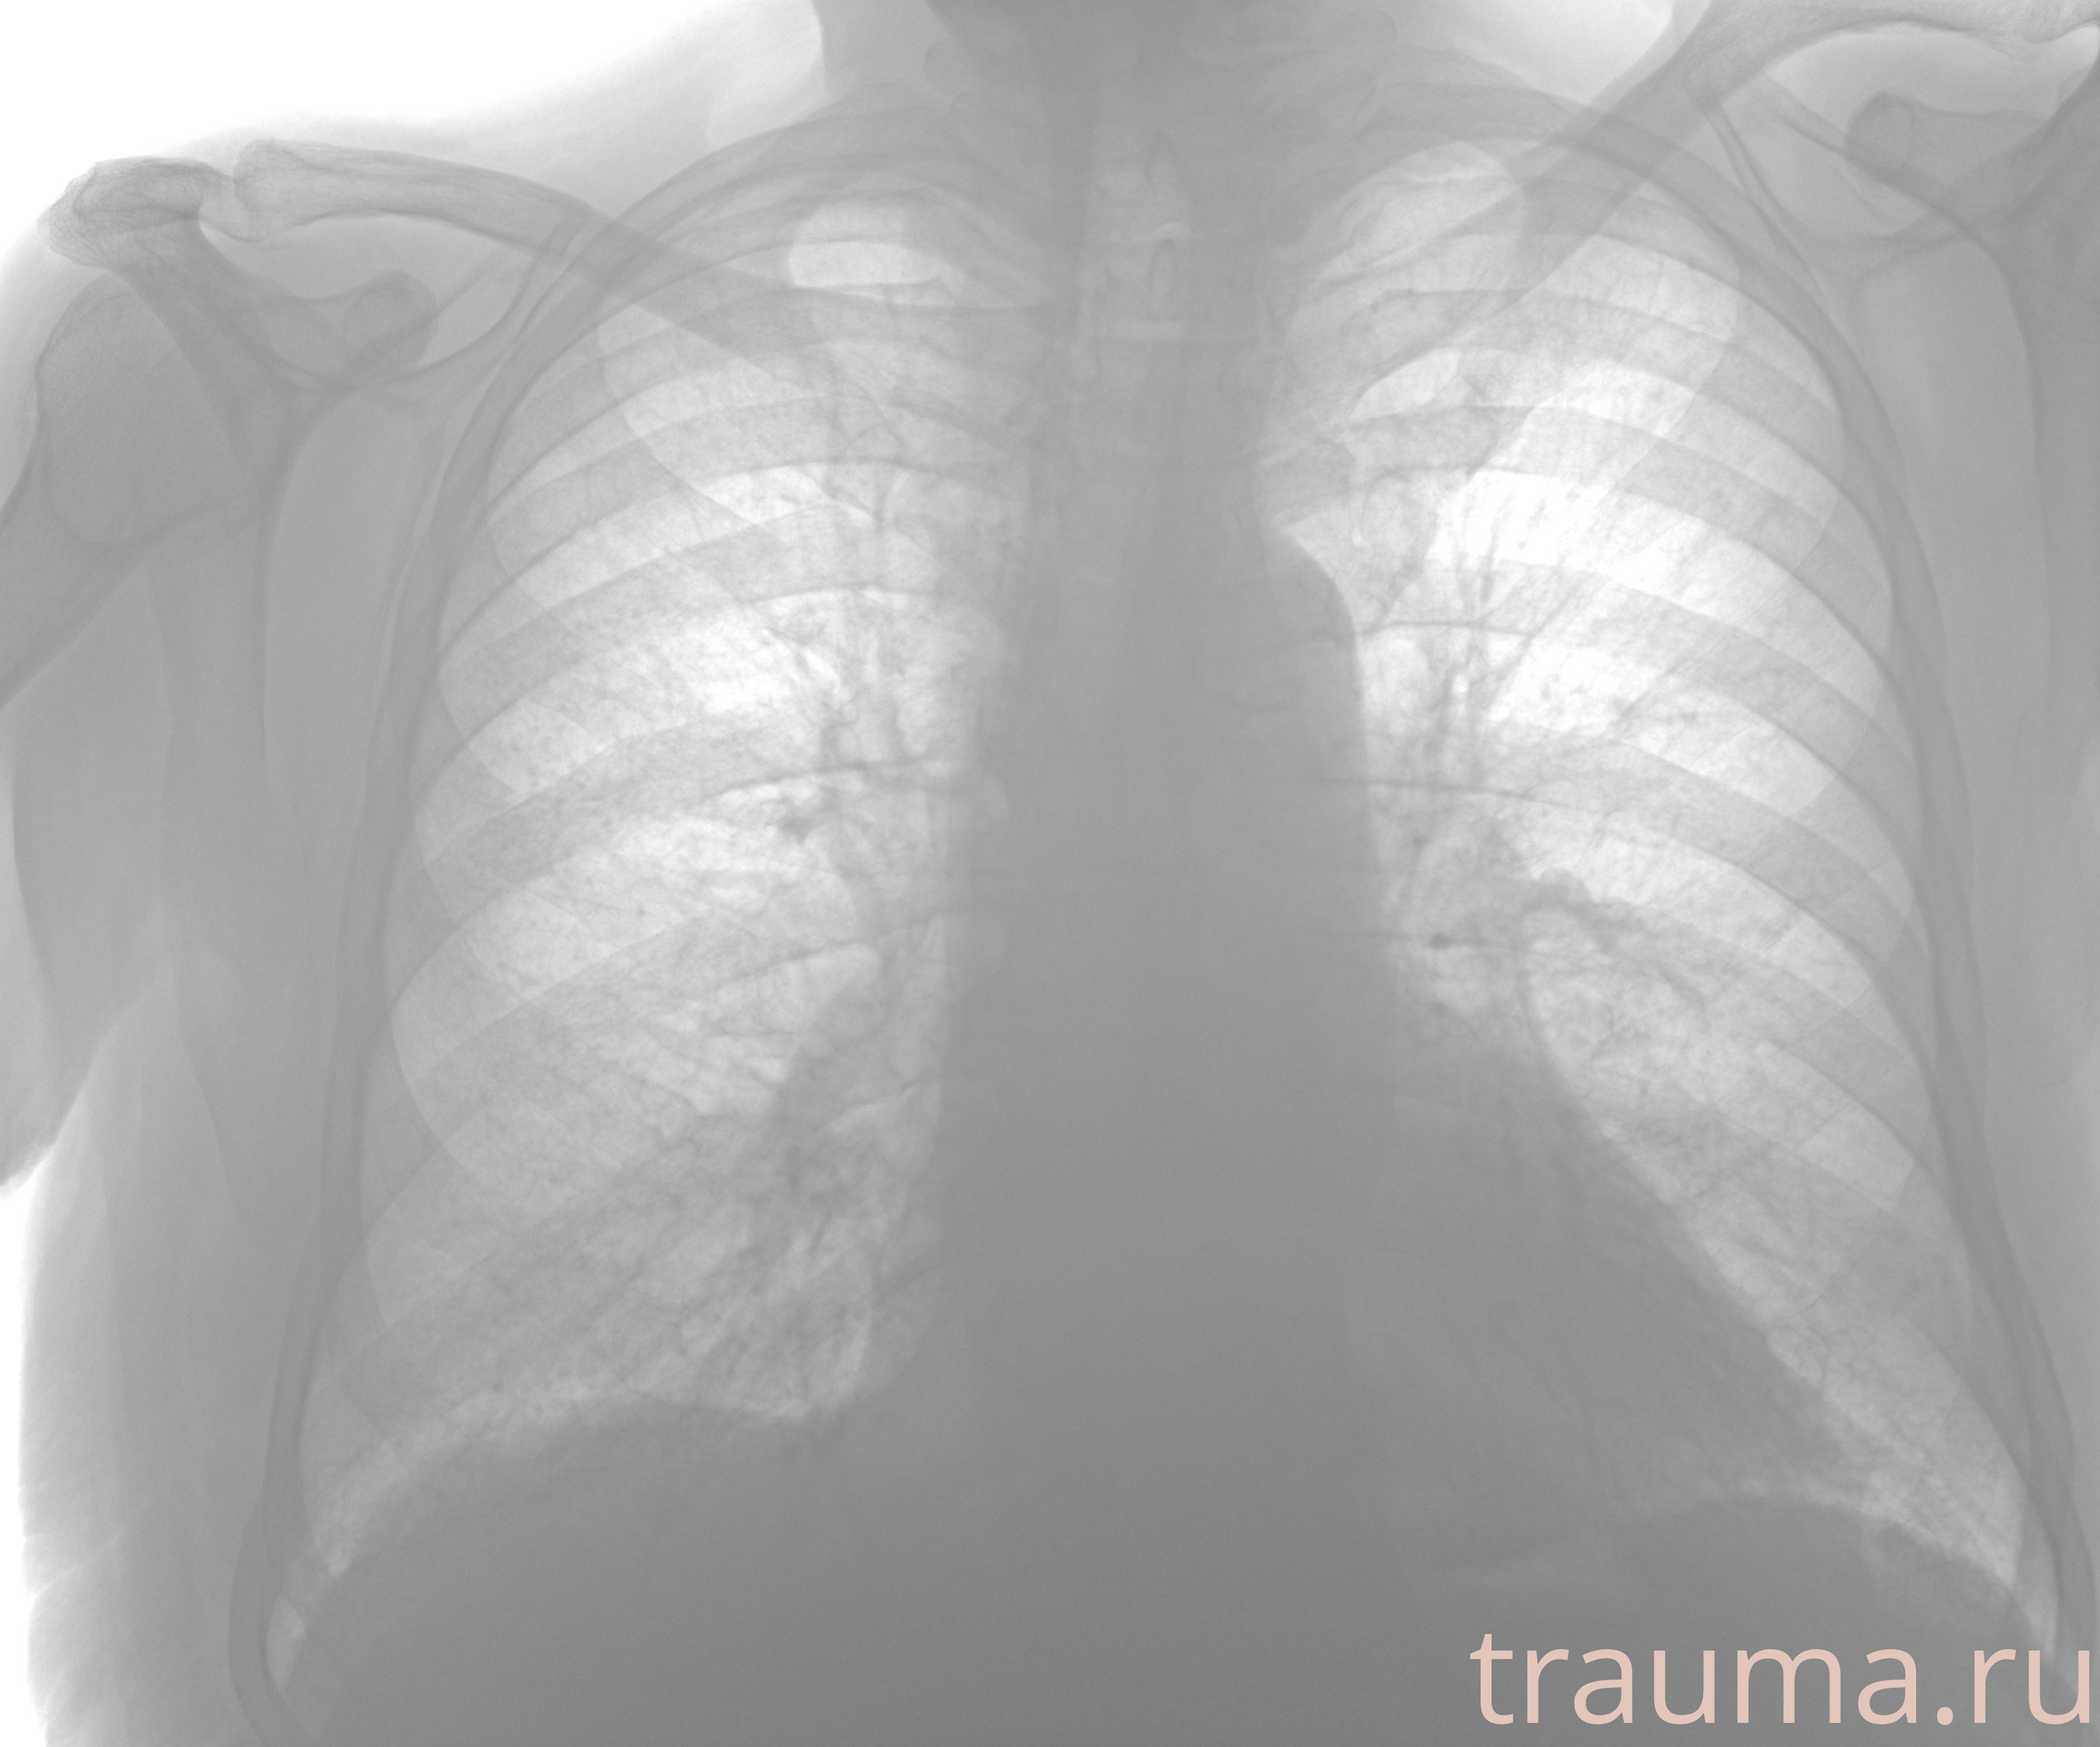

Рентгенограммы

Рентген на дому: по вашему адресу приезжает врач-рентгенолог, травматолог-ортопед с мобильным рентгеновским аппаратом, проводит диагностику травмы или заболевания, делает необходимые рентгенограммы, дает рекомендации по дальнейшему лечению. Получить качественные снимки в домашних условиях возможно благодаря уникальной методике, разработанной МосРентген Центром для института  Склифосовского

Яркость: 1   Контраст: 1   Инвертировать: 0 Увеличение: 1

Перетаскивайте мышь вверх/вниз для контраста, влево/право для яркости. Прокрутка колесом изменяет масштаб. Нажмите Сбросить для возврата к исходному изображению. При увеличении держите мышь в той области, которую хотите рассмотреть.